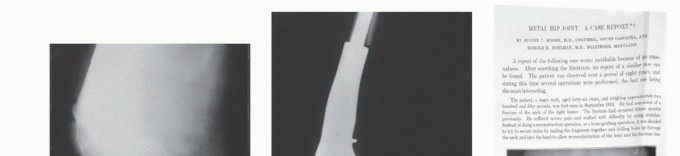

- Hemiarthroplasty: Get the b tech fig on Hip Implant Types